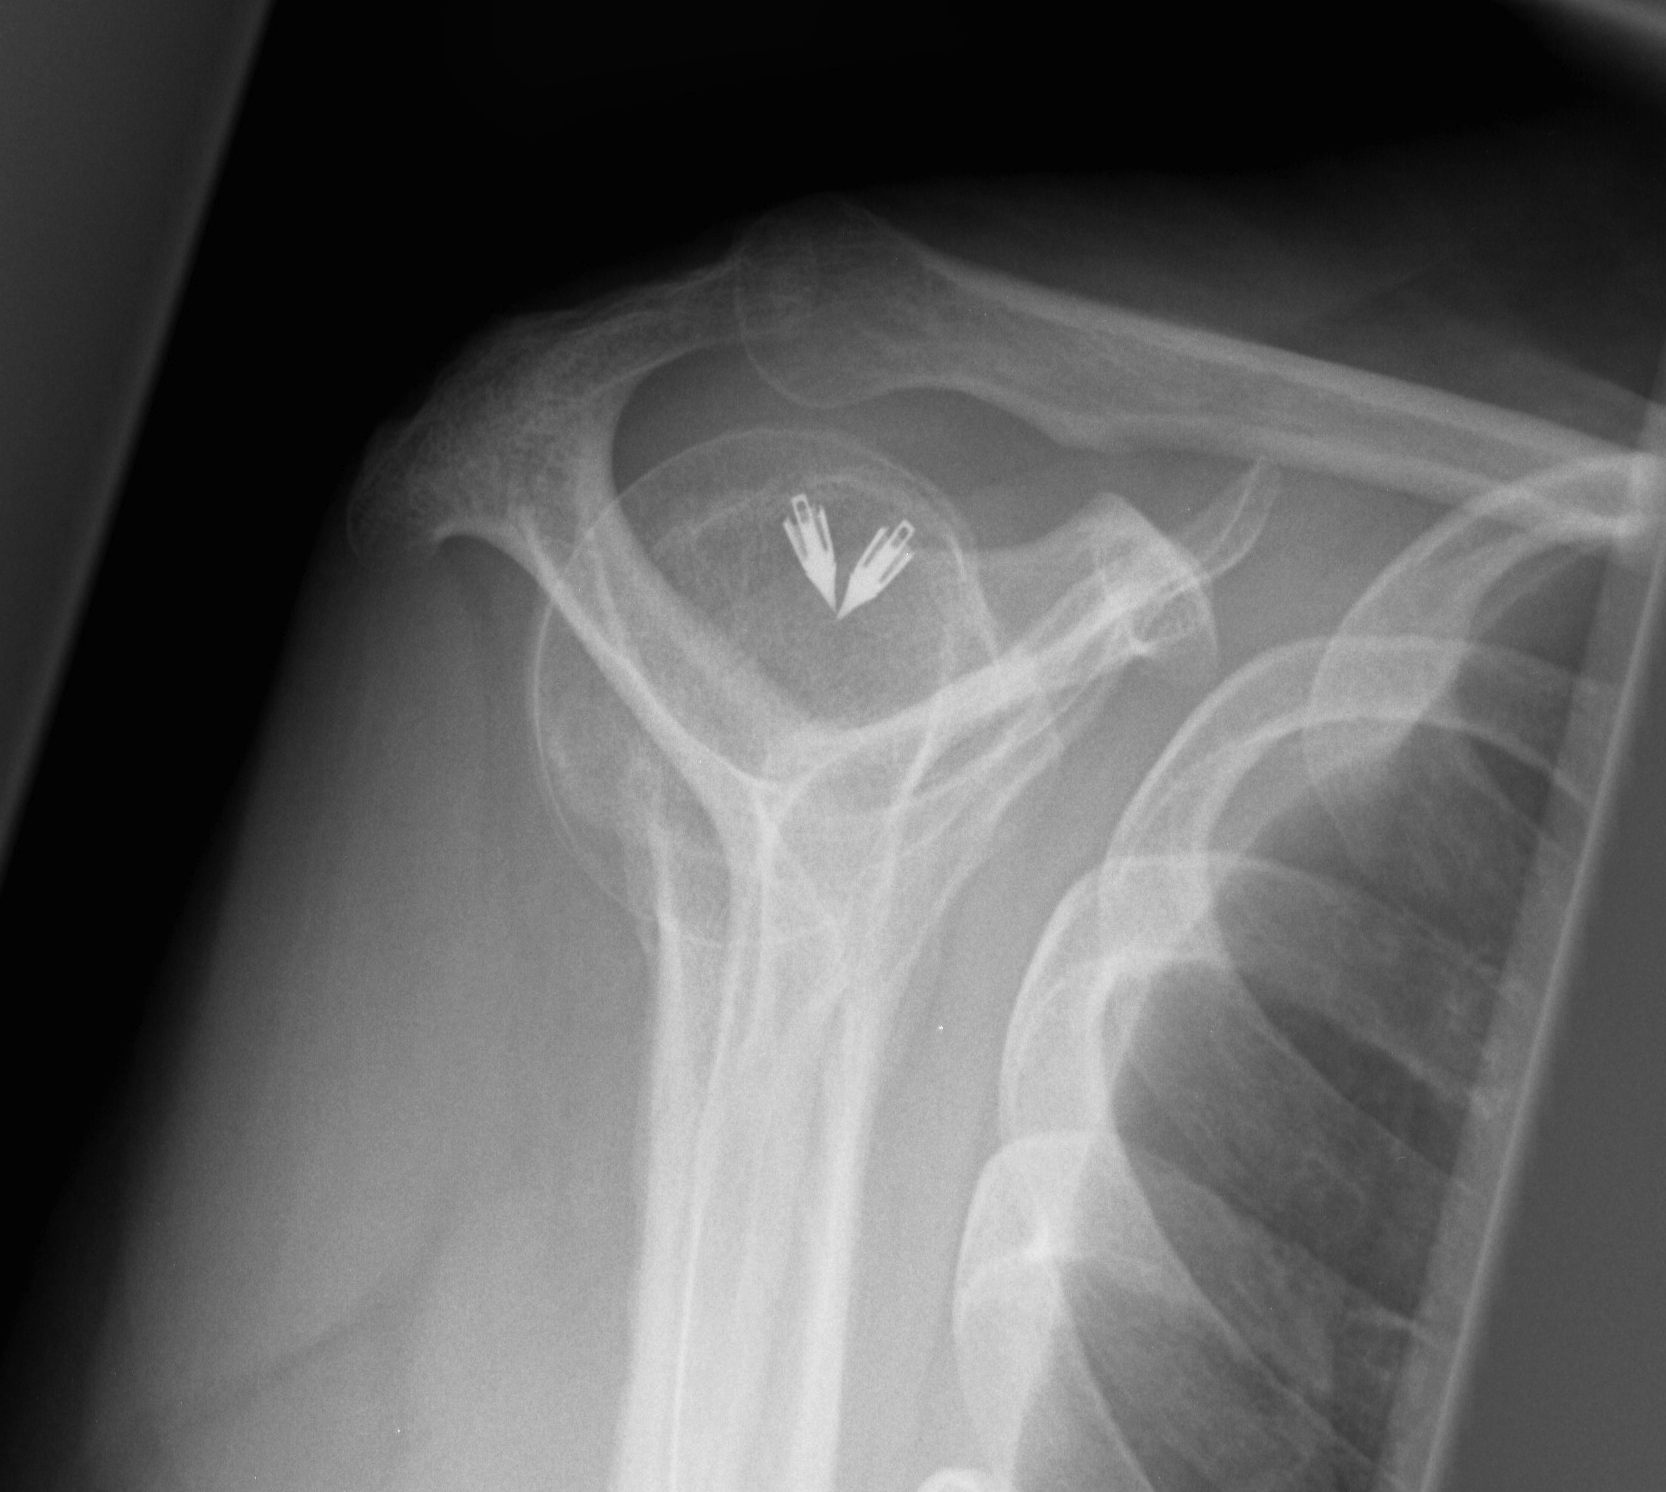

Arthroscopic Supraspinatous Repair

Technique

Glenohumeral joint

- inspect subscapularis

- evaluate SLAP / LHB tendinosis - tenotomy / tenodesis

Subacromial joint

- bursectomy for visualization

- acromioplasty if acromial spur

- debride footprint to bleeding bone

- +/- microfracture / K wire of footprint / marrow stimulation